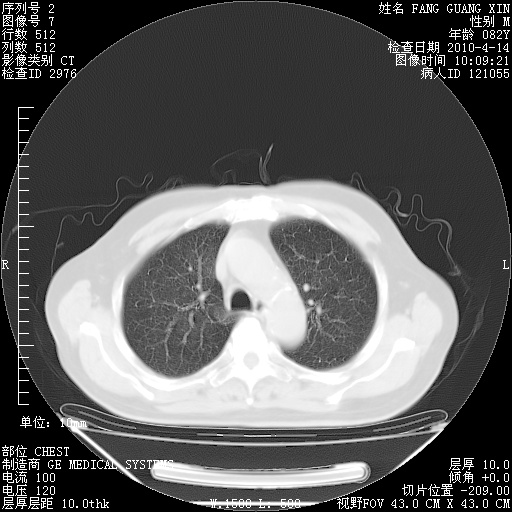

4月14日肺部CT

肺部CT平扫未见异常。